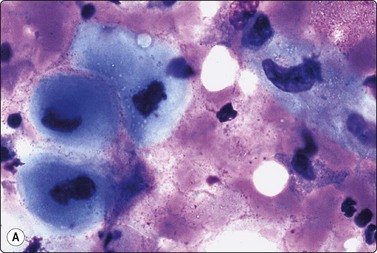

image

Fig. 5.1 Lymphoid globules

Numerous spherical fragments of blue cytoplasm of variable sizes dispersed between the lymphoid cells; some nuclear fragments. Large cell lymphoma of tonsil (MGG, HP).

Fine needle biopsy samples of lymphoid tissue, nodal or extranodal, benign or malignant, as a rule have a very high cell content. This is obvious to the naked eye as the aspirate is smeared. It looks like a film of slimy material which turns gray on drying. The cytoplasm of lymphoid cells is fragile. Many cells are represented by naked nuclei or have only a small rim of cytoplasm. A variable number of rounded cytoplasmic fragments measuring up to 8 microns in diameter are scattered in the background (Fig. 5.1). The cytoplasmic fragments were named ‘lymphoglandular bodies’ by Söderström. The term ‘lymphoid globules’ is prefered since they are present in smears from any lymphoid infiltration, not only from lymph nodes. The fragments stain an uniform pale blue, identical to the cytoplasm of intact cells, with Giemsa stain. They differ from necrotic debris by their regular round shape and their uniform staining. Necrotic debris and nuclear fragments (karyorrhexis and apoptotic bodies) are characteristic of smears of small cell undifferentiated carcinoma (Fig. 5.2). The recognition of ‘lymphoid globules’ is of diagnostic value in the distinction of lymphoma from anaplastic carcinoma and some other tumors.